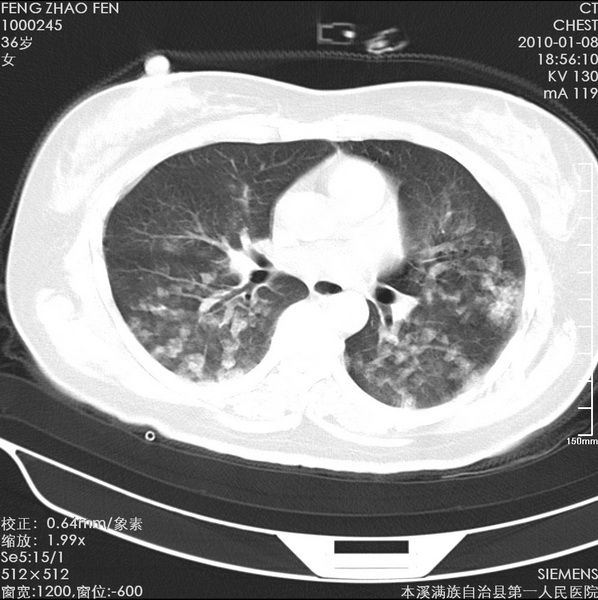

标题: CT24051:双肺多发斑片状阴影 [打印本页]

标题: CT24051:双肺多发斑片状阴影

女、36、咳嗽、咯血,余不详。